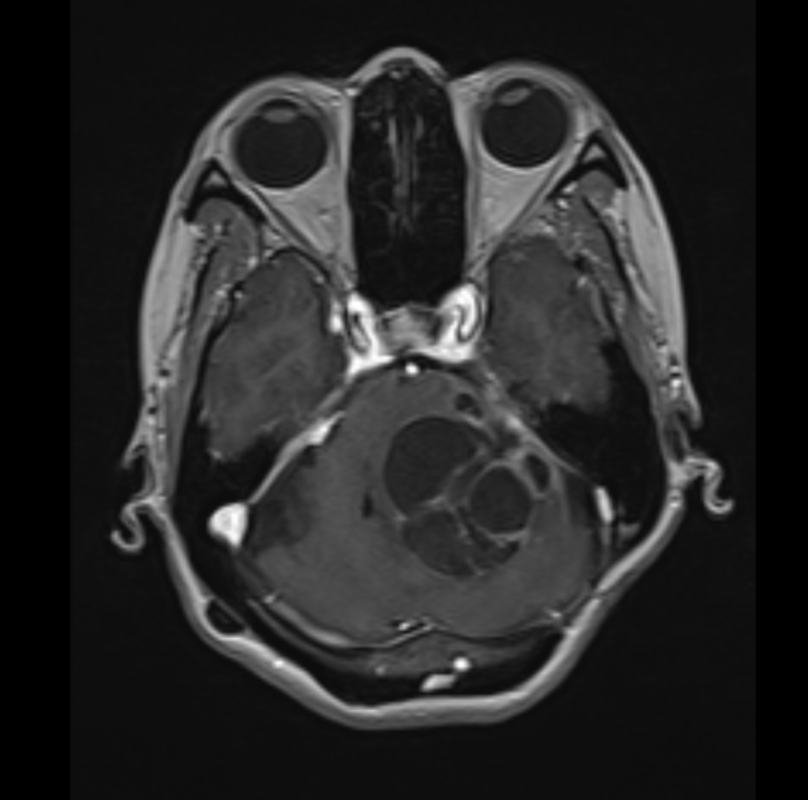

聴神経腫瘍(再発、巨大)

コロナが明け、久々のハノイ出張です。40代女性の再発聴神経腫瘍。聴力障害はありましたが、顔面神経麻痺はなく、非常に大きく、かつ癒着も強く、手術に難渋しましたが、何とか顔面神経機能を温存し全摘出しました。